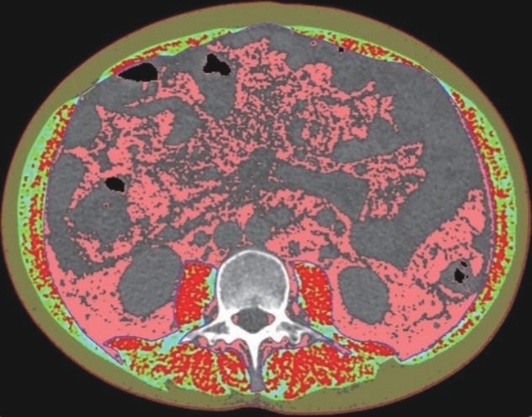

目的 本文旨在肌肉脂肪浸润的基础上,利用分层分析的方法将肌肉内部按照不同的密度范围划分成不同的亚分区,进一步研究肌肉密度改变对原位肝移植术(OLT)后并发症(Clavien-Dindo≥Ⅲ)的影响。 方法 回顾性分析2013年5月—2020年9月于吉林大学第一医院行OLT的145例患者,以患者腰3椎体水平最大层面的CT平扫图像作为原始数据,利用Neusoft Fatanalysis软件对图像进行相关肌肉参数的测量。符合正态分布的计量资料组间比较采用成组t检验;不符合正态分布的组间比较采用Mann-Whitney U秩和检验。计数资料组间比较采用χ2或Fisher检验。利用RIAS软件进行临床特征提取及分析建模,分别建立逻辑回归(LR)、支持向量机(SVM)、随机森林(RFC)3种机器学习模型,并绘制不同模型的受试者操作特征曲线(ROC曲线)、校正曲线、决策分析曲线,计算ROC曲线下面积(AUC)、灵敏度、特异度、精确率、F1分数、准确率。 结果 采用肌肉分层分析前的7种临床特征建立LR-C、SVM-C、RFC-C 3种机器学习模型,其中RFC-C模型测试集的AUC值为0.803、灵敏度0.588,特异度0.778。采用肌肉分层分析后的16种临床特征建立的LR-CS、SVM-CS、RFC-CS模型中,LR-CS及SVM-CS模型测试集的AUC值较高,均为0.852,灵敏度分别为0.765、0.706,特异度分别为0.889、0.926,通过对比肌肉分层分析前后各模型测试集的AUC、灵敏度、特异度、精确率、F1分数、准确率后发现,肌肉分层分析后预测模型的参数均有所提升。通过对比各预测模型的决策分析曲线和校正曲线,发现LR-CS及SVM-CS模型对于预测OLT患者术后并发症(Clavien-Dindo≥Ⅲ)具有良好效能。 结论 在肌肉脂肪浸润的基础上,利用分层分析的方法将肌肉内部按照不同的密度划分成不同子区,对于OLT患者术后并发症有一定预测价值。 Abstract:Objective To divide the muscle into different subzones according to different density ranges using the stratified analysis on the basis of myosteatosis, and to investigate the effect of muscle density changes on complications (Clavien-Dindo grade ≥Ⅲ) after orthotopic liver transplantation (OLT). Methods A retrospective analysis was performed for the medical records of 145 patients who underwent OLT in The First Hospital of Jilin University from May 2013 to September 2020, and with the plain CT scan images of the largest level of lumbar 3 vertebrae of each patient as the original data, Neusoft Fatanalysis software was used to measure related muscle parameters. The independent-samples t test was used for comparison of normally distributed continuous data between two groups, and the Mann-Whitney U test was used for comparison of non-normally distributed continuous data between two groups. The chi-square test or Fisher test was for comparison of categorical data between two groups. RIAS software was used to extract clinical features and perform analysis and modeling, and three machine learning models of logistic regression (LR), support vector machine (SVM), and random forest (RFC) were constructed. The receiver operating characteristic (ROC) curve, the calibration curve, and the decision curve were plotted for each model to calculate the area under the ROC curve (AUC), sensitivity, specificity, precision, F1 score, and accuracy. Results The three machine learning models of LR-C, SVM-C, and RFC-C were established based on the 7 clinical features before muscle stratification analysis, among which the RFC-C model had an AUC of 0.803, a sensitivity of 0.588, and a specificity of 0.778 in the test set. Among the models of LR-CS, SVM-CS, and RFC-CS established based on the 16 clinical features after muscle stratification analysis, the LR-CS and SVM-CS models had an AUC of 0.852 in the test set, with a sensitivity of 0.765 and 0.706, respectively, and a specificity of 0.889 and 0.926, respectively. Comparison of the AUC, sensitivity, specificity, precision, F1 score, and accuracy of each model in the test set before and after muscle stratification analysis showed that there were improvements in the parameters of the predictive model after muscle stratification analysis. Comparison of the decision curves and calibration curves of each predictive model showed that the LR-CS and SVM-CS models had good efficacy in predicting postoperative complications (Clavien-Dindo grade≥Ⅲ) in OLT patients. Conclusion On the basis of myosteatosis, the division of the muscle into different subzones according to different densities using the stratified analysis has a certain value in predicting postoperative complications in patients with OLT. -

表 2 肌肉分层分析后测量得到的影像学相关参数

指标 训练集(n=101) 测试集(n=44) P值1) 并发症组(n=32) 非并发症组(n=69) P值 并发症组(n=17) 非并发症组(n=27) P值 NAMA-SMI(cm2/m2) 23.44±1.40 30.04±0.89 <0.001 22.02(17.62~26.70) 28.73(20.13~36.41) 0.038 0.594 NAMA百分比 0.58±0.02 0.73±0.01 <0.001 0.58±0.04 0.73±0.02 0.001 0.703 NAMA-SMRA(HU) 47.52±0.75 49.10±0.40 0.044 47.70±0.83 48.36±0.70 0.548 0.452 LAMA-SMI(cm2/m2) 11.09±0.59 8.60±0.40 0.002 11.60(6.95~12.58) 8.38(6.12~9.51) 0.047 0.456 LAMA百分比 0.28±0.01 0.21±0.01 0.002 0.59(0.46~0.65) 0.74(0.66~0.81) 0.025 0.909 LAMA-SMRA(HU) 17.68(17.02~18.10) 18.02(17.78~18.56) 0.003 17.34±0.22 18.02±0.15 0.011 0.293 HAMA-SMI(cm2/m2) 4.76(3.77~7.39) 2.10(1.74~2.15) <0.001 6.60(3.59~7.94) 1.87(1.70~2.60) <0.001 0.834 HAMA百分比 0.13(0.11~0.17) 0.05(0.04~0.07) <0.001 0.16(0.09~0.20) 0.05(0.04~0.08) <0.001 0.707 HAMA-SMRA(HU) -23.0(-30.2~-15.4) -13.0(-13.8~-10.0) <0.001 -28.0(-31.3~-13.5) -12.4(-13.6~-9.7) <0.001 0.896 注:1)训练集与测试集比较。